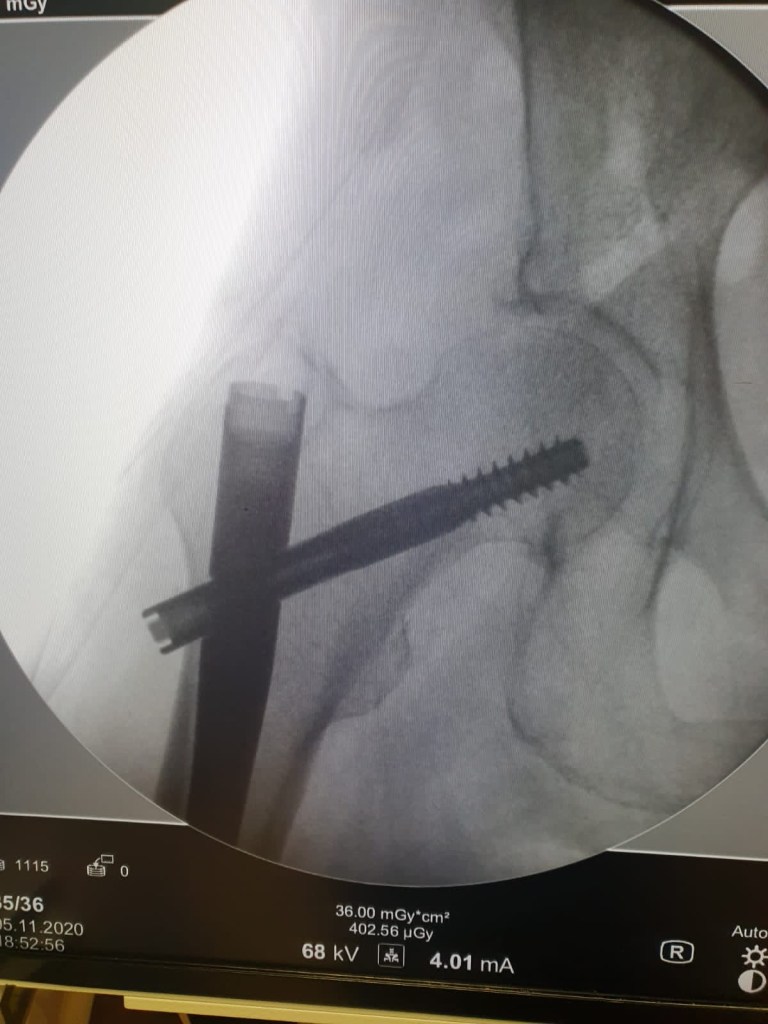

Vous trouverez ci après les interventions réalisées par le Dr DOLEAC